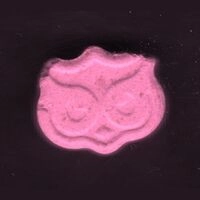

Baza tabletek Ecstasy zawiera analizy laboratoriów i użytkowników. Wyniki to ostrzeżenia. Żadna substancja nie jest w 100% bezpieczna. Badaj substancje przed zażyciem. Sprawdź narkotest.

Zastrzeżenie: Informacje przedstawione na tej stronie nie mają na celu promocji zażywania narkotyków. Wiele wymienionych substancji jest nielegalne według prawa krajowego i międzynarodowego, posiadanie tych substancji jest karane przez prawo. Nigdy nie zakładaj, że substancja jest bezpieczna. Tabletki Ecstasy (extasy, XTC, emka, molly) powinny zawierać MDMA ale stężenie, czystość i domieszki bardzo się różnią, nawet jeśli próbki pochodzą z tego samego źródła lub wyglądają podobnie. Chemical Safety sp. z o.o. stanowczo odradza używania jakichkolwiek substancji psychoaktywnych – legalnych lub nielegalnych. Zażywanie substancji psychoaktywnych zawsze jest możliwym do uniknięcia ryzykiem dla zdrowia.